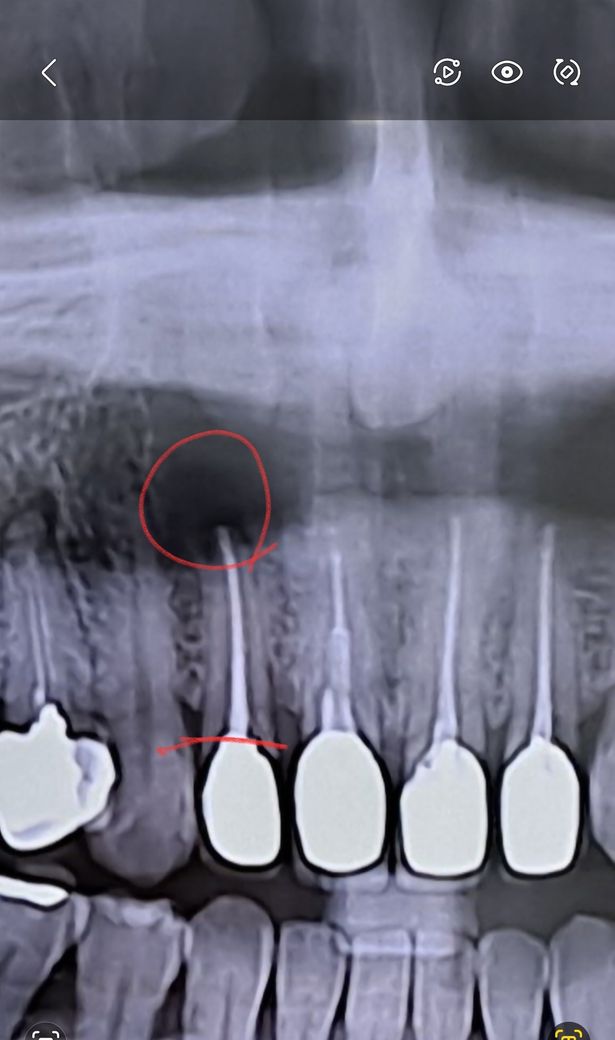

옉스레이상 빨간동그라미 친부분 염증이맞나요??

파노라마 사진상으로는 확인이 안됩니다. 저부분은 코떄문에 저렇게 보이는경우도 있습니다.

X-ray 상 염증이 크지 않아 보이며, 현재 통증이나 고름이 없는 상태라면 재 신경치료 없이 크라운진행이 가능하기도 합니다. 하지만 염증이 있는지 다시 한번 치과에 방문하여 확인을 해보고, 재신경치료 여부를 결정하길 권합니다.